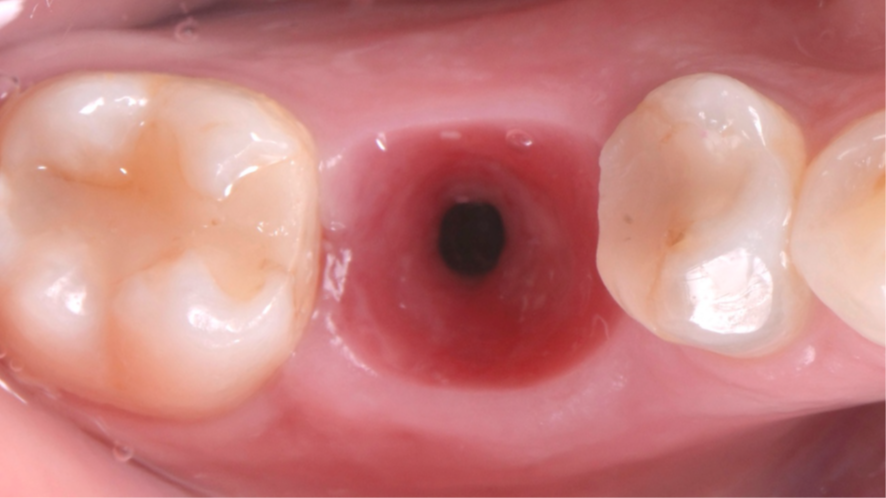

Mulher de 48 anos, sem antecedentes médicos relevantes, procurou atendimento odontológico com queixa principal de dor contínua em região do primeiro molar inferior direito. Na avaliação clínica foi observado uma fístula na vestibular do dente 46 (Figura 1) e a tomografia revelou uma fratura longitudinal, comprometendo a manutenção deste dente (Figura 2). Confirmada a necessidade de exodontia, foi planejada a instalação de um implante imediato e a confecção de um cicatrizador personalizado diretamente na plataforma do implante com um pilar provisório de titânio. Foi realizada uma extração dentária minimamente traumática visando preservar a integridade dos tecidos moles e duros circundantes (Figuras 3 e 4).

Após a instalação do implante, um cicatrizador foi colocado somente para proteger a conexão morse do implante e o GAP foi preenchido com Extra Graft 1g (Figura 7). Como foi alcançada uma alta estabilidade primária, um pilar provisório de titânio foi instalado e nele foi confeccionado um cicatrizador personalizado com resina fluida (Figuras 8, 9 e 10).